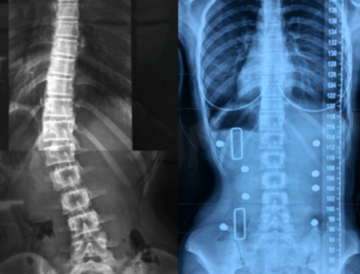

أبريل 24, 2026 التنبؤ بنتائج حزام اعوجاج العمود الفقري :الفرق بين الأشعة داخل الحزام وخارجه… scoliosis, اعوجاج العمود الفقري, الجنف لا يوجد تعليق 7 المشاهدات التنبؤ بنتائج حزام اعوجاج العمود الفقري :الفرق بين الأشعة داخل الحزام وخارجه يُعد اعوجاج العمود الفقري عند المراهقين من أكثر حالات التشوهات الشائعة خلال مرحلة النمو، ويُعرف طبيًا باسم “الجنف مجهول السبب عند المراهقين”.